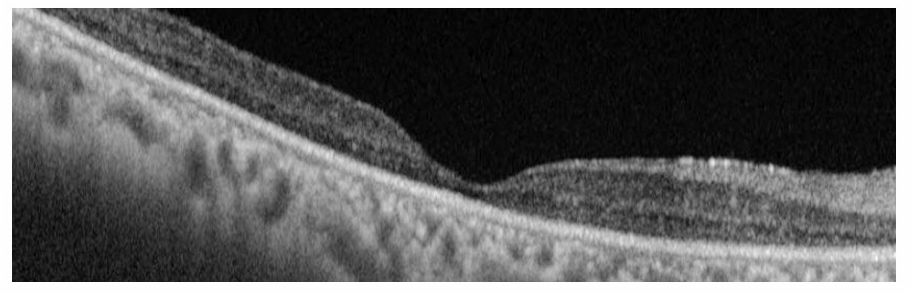

進行の早かった治療抵抗性の癌関連網膜症の1例。71歳女性、両眼のかすみがあり、1週間後硝子体混濁が出現し紹介となった。1か月前まで子宮癌の治療を受けていた。両眼とも視力は指数弁、眼底は硝子体混濁以外に所見なく、OCTで網膜外層障害が非常に強く、ERGはフラット。発症2週間後にステロイドパルス療法を開始したが、効果なく光覚弁となった。治療後、外顆粒層は消失していた(写真下段)。